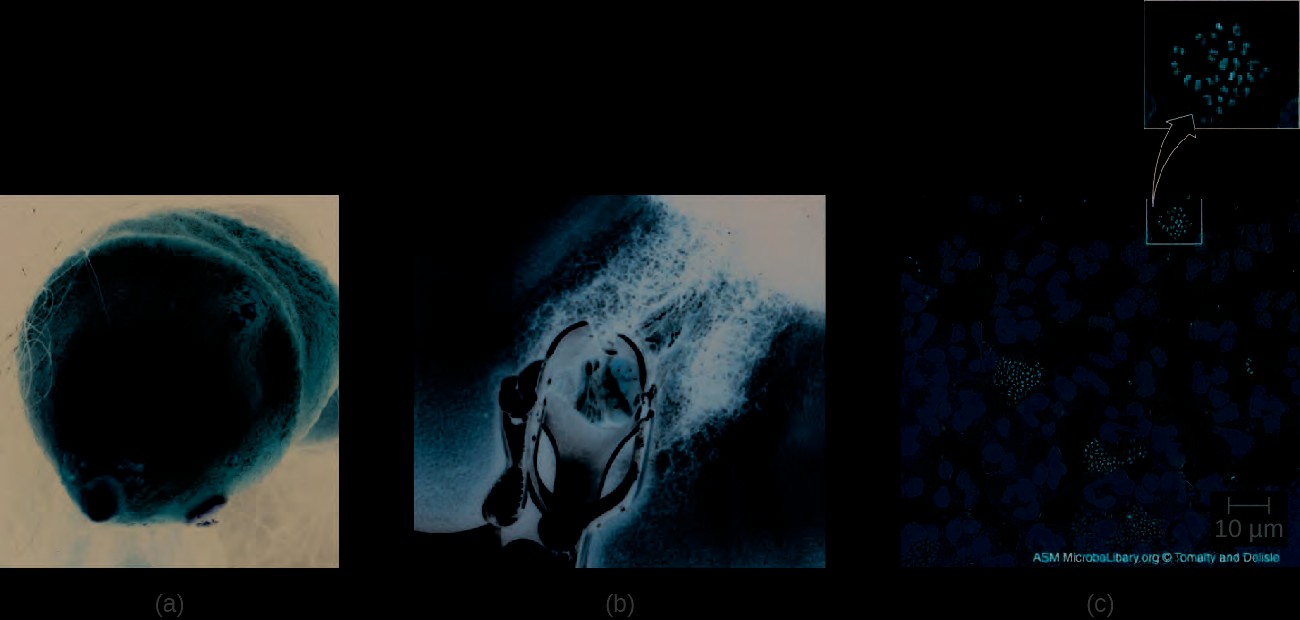

Only one major fungal pathogen affects the urogenital system. Candida is a genus of fungi capable of existing in a yeast form or as a multicellular fungus. Candida spp. are commonly found in the normal, healthy microbiota of the skin, gastrointestinal tract, respiratory system, and female urogenital tract (Figure 23.21). They can be pathogenic due to their ability to adhere to and invade host cells, form biofilms, secrete hydrolases (e.g., proteases, phospholipases, and lipases) that assist in their spread through tissues, and change their phenotypes to protect themselves from the immune system. However, they typically only cause disease in the female reproductive tract under conditions that compromise the host’s defenses. While there are at least 20 Candida species of clinical importance, C. albicans is the species most commonly responsible for fungal vaginitis.

As discussed earlier, lactobacilli in the vagina inhibit the growth of other organisms, including bacteria and Candida, but disruptions can allow Candida to increase in numbers. Typical disruptions include antibiotic therapy, illness (especially diabetes), pregnancy, and the presence of transient microbes. Immunosuppression can also play a role, and the severe immunosuppression associated with HIV infection often allows Candida to thrive. This can cause genital or vaginal candidiasis, a condition characterized by vaginitis and commonly known as a yeast infection. When a yeast infection develops, inflammation occurs along with symptoms of pruritus (itching), a thick white or yellow discharge, and odor.

Diagnosis of vaginal candidiasis can be made using microscopic evaluation of vaginal secretions to determine whether there is an excess of Candida. Culturing approaches are less useful because Candida is part of the normal microbiota and will regularly appear. It is also easy to contaminate samples with Candida because it is so common, so care must be taken to handle clinical material appropriately. Samples can be refrigerated if there is a delay in handling. Candida is a dimorphic fungus, so it does not only exist in a yeast form; cultivation can be used to identify chlamydospores and pseudohyphae, which develop from germ tubes (Figure 23.22). The presence of the germ tube can be used in a diagnostic test in which cultured yeast cells are combined with rabbit serum and observed after a few hours for the presence of germ tubes. Molecular tests are also available if needed. The Affirm VPII Microbial Identification Test, for instance, tests simultaneously for the vaginal microbes C. albicans, G. vaginalis (see Bacterial Infections of the Urinary System), and Trichomonas vaginalis (see Protozoan Infections of the Urogenital System).

Figure 23.21 Candida blastospores (asexual spores that result from budding) and chlamydospores (resting spores produced through asexual reproduction) are visible in this micrograph. (credit: modification of work by Centers for Disease Control and Prevention)